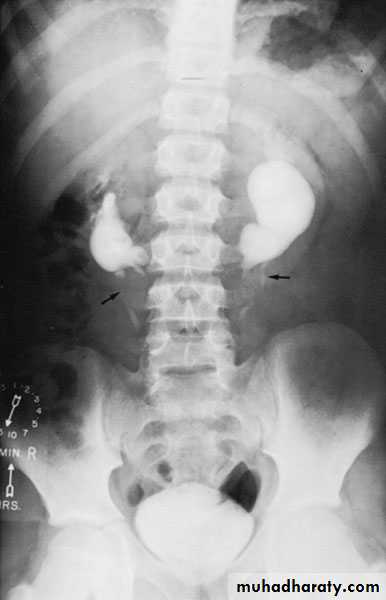

Ureteropelvic Junction (UPJ)(PUJ) Obstruction (stenosis)

Urology

The most common cause of significant dilation of the collecting system in the fetal kidney

Boys > Girls

Left-sided lesions predominate

15% bilateral

PUJ Obstruction – gross pathology

SYMPTOMS/PRESENTATION

Most infants are asymptomatic and most children are discovered because of their symptoms

Episodic flank or upper abdominal pain, sometimes associated with nausea and vomiting

DIAGNOSIS

U/S: hydronephrosis

IVU: diagnostic , hydronephrosis with

fixed stenotic segment or complete

obstruction

CT scan: hydronephrosis that ends